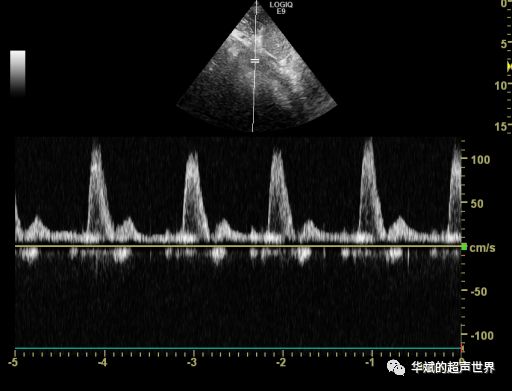

图1 正常腹主动脉血流频谱

正常膈肌水平腹主动脉血流血流频谱我们再熟悉不过,多普勒显像近似于高阻力的外周肢体动脉,表现为心脏收缩所致的高速正向血流,随后为舒张早期短暂反向血流,最后是舒张晚期低速前向血流,即三相波或双相波(图1)。但如果腹主动脉血流频谱出现低流速低搏动的“小慢波”改变(图 2),到底发生了什么?本文通过回顾性分析 17 例腹主动脉“小慢波”改变患儿的声像图特征,探讨异常频谱形成的原因,旨在通过间接征象提高相应先天性心脏病的超声检出率及准确率。